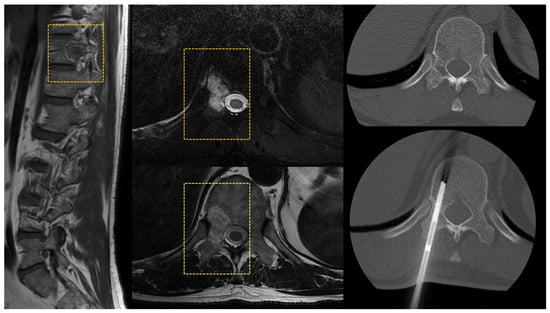

2.3. The Spine